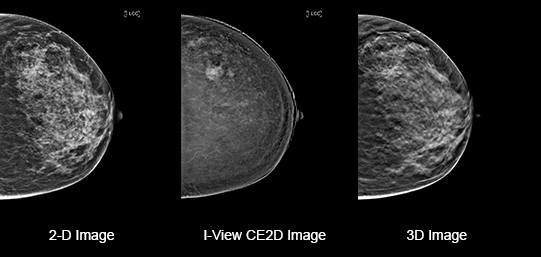

Eliminates Structural Background

Acquire a pair of high- and low-energy images in rapid succession. This allows for regions of abnormal blood flow to be displayed by subtracting the background breast parenchyma.

Contrast-enhanced mammography enhances visualization and may uncover hidden abnormalities – a crucial factor in reducing missed and or underdiagnosed cancers.